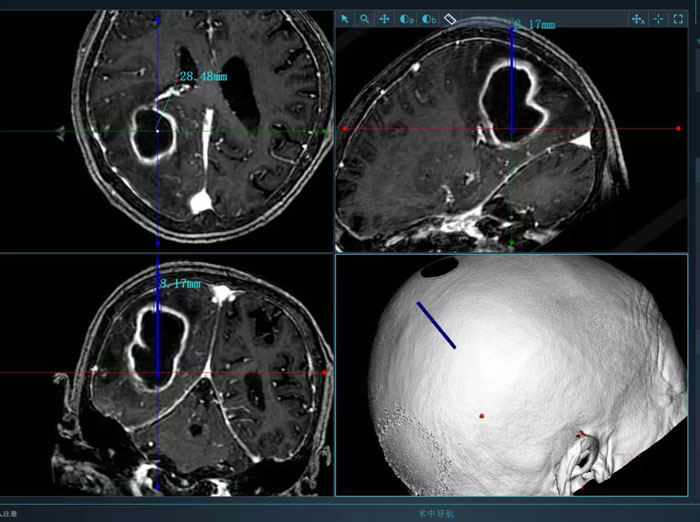

病例2.患者為74歲老年女性,術前因高熱入院,檢查發現腦膿腫。該患者體質較差,而且膿腫體積大,形態不規則,傳統穿刺引流方式難以完全將膿腫引流徹底,且易造成膿腫擴散,引起嚴重不良后果。續繼軍主任決定采用智能機器人輔助穿刺,術前借助智能機器人手術計劃系統避開腦重要功能區及血管,精心設計了最優穿刺路徑。續繼軍主任帶領丁鵬主治醫師在機器人引導下行膿腫穿刺引流,一次穿刺到位,術中引流出腦膿腫25ml。術后,復查CT顯示引流管到達預定靶點,位置良好,膿腫引流滿意,患者顱高壓癥狀明顯緩解,腦膿腫得到有效控制。